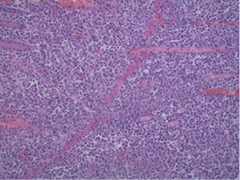

A 46-years-old female patient presented to the emergency department with clinical signs of intestinal obstruction. The patient reported cramp and abdominal pain, and absence of flatus and stool passage one day prior to the exam. She had no previous abdominal surgery nor visible groin herniation on physical examination. The serum analysis showed C-reactive protein value of 5.80 (0.0–5.0 mg/L) and serum Iron level of 5.80 (6.6–28.3 μmol/L). Plain abdominal upright X-ray image confirmed the suspicion for intestinal obstruction (Figure 1).

Figure 1. Plain abdominal X-ray with small bowel air-liquid levels